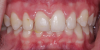

(1.) Pretreatment retracted view of a 16-year-old female patient who presented with generalized spacing between her maxillary anterior teeth. because she was still in her growth phase, milled composite veneers were planned as a transitional treatment. These would be replaced with definitive ceramic veneers once her growth phase was completed.

Figure 1